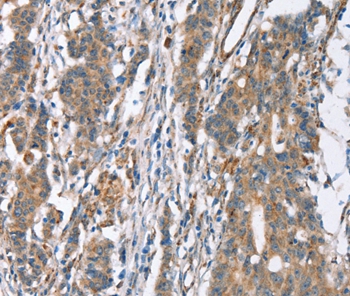

Immunohistochemical analysis of paraffin-embedded Human gastric cancer tissue using #37439 at dilution 1/30.